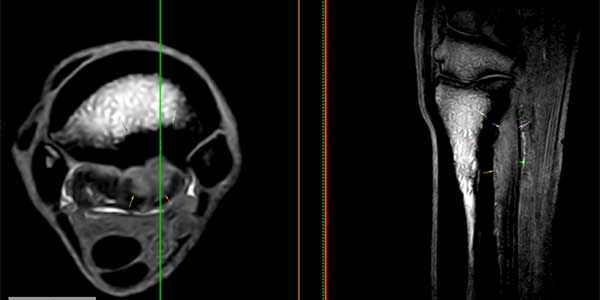

Clichés IRM (de gauche à droite : STIR en coupe transversale, GRE en reconstruction sagittale, PD en coupe transversale) d’un chien présentant une pathologie dégénérative chronique des fléchisseurs du carpe (fléchisseur ulnaire du carpe) où l’on peut observer un épaississement sévère du tendon qui présente un mélange d’intensités hétérogènes.